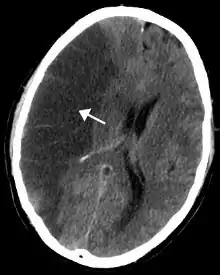

.jpg.webp)

La consommation de tabac est la première cause de cancer connue dans le monde. Elle est impliquée dans 33,9 % des cancers mondiaux[40].

- Il s'agit d'une cause importante des cancers des poumons. En France, 25 000 décès imputables au tabac sont dus au cancer du poumon (seuls 10 % des cancers du poumon ne sont pas imputables au tabagisme). Les cigarettes actuelles sont plus toxiques qu'auparavant. À ce titre les fumeurs ont plus de risques d'avoir un cancer du poumon qu'en 1964 bien qu'ils fument moins[24].